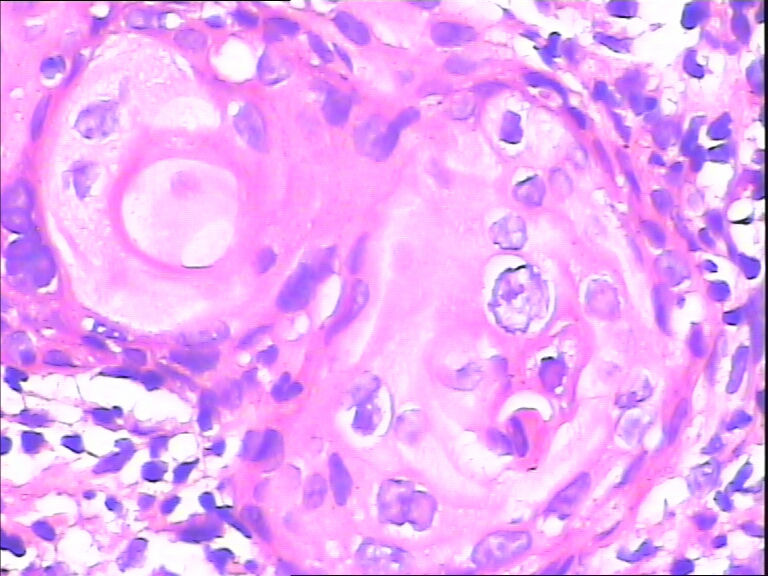

45y,触血,宫颈多点活检。

HPV感染

不同级别的CIN,局灶已达到CIN3。

HSIL伴

考虑HPV感染,应该没有高级别上皮内瘤变,建议做HPV检测。

湿疣改变

HPV感染。局部已达到CIN2-3

CINⅡ,提示HPV感染。

主要考虑HPV感染引起的细胞改变。

慢性宫颈炎伴HPV感染改变、腺体鳞状化生。

HPV感染。灶性CIN2-3